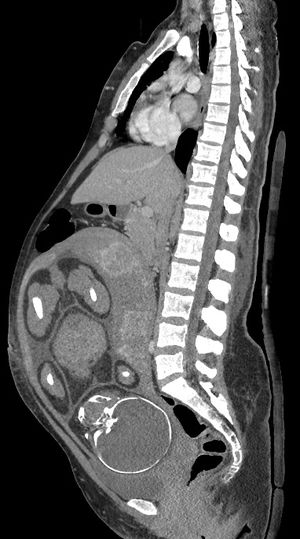

- ينتج التصوير الشعاعي والتصوير المقطعي المحوسب والطب النووي درجة من التعرض للإشعاع المؤين، ولكن مع بعض الاستثناءات بجرعات الطاقة الممتصة أقل بكثير من ما يرتبط بضرر الجنين.[1] يشار إليها عندما لا يكون التصوير بالموجات فوق الصوتية أو التصوير بالرنين المغناطيسي متاحًا بسهولة أو غير ممكن للسؤال التشخيصي في متناول اليد.[1]

تصوير مقطعي محوسب | |

البطني | 1.3 - 35[1] |

الحوض | 10 - 50[1] |